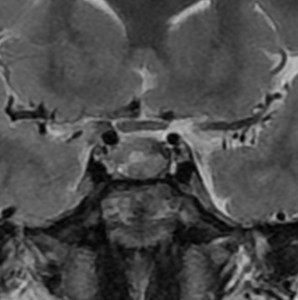

29歳の女性が高プロラクチン血症による月経不順で発症しました。視野検査では両耳側半盲が認められました。

手術所見では,多量のコレステリン結晶が流出しました。腫瘍実質は硬く正常下垂体との剥離はできませんでした。黄色肉芽種の可能性もあるので,あ全摘出にとどめて手術を終了しました。T2強調画像で黒い低信号の縁取りがあり内部に不均一なのう胞内容液が見えるのが特徴とも言えます。

3年後の画像です。腫瘍の再燃増大はありませあん。視野は正常化して,下垂体機能も正常化しホルモン補充はありません。